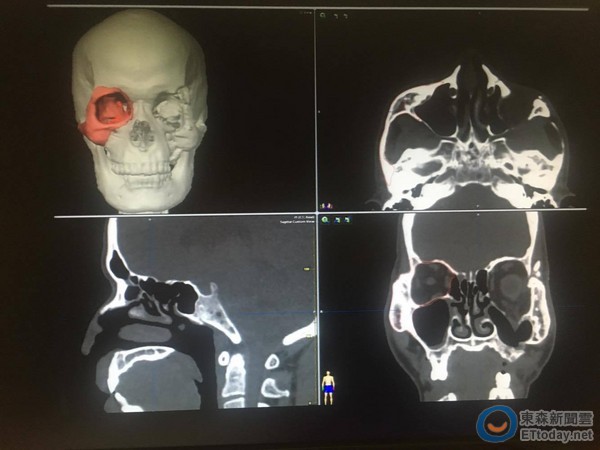

50歲的雕刻師傅彭先生,因為車禍撞傷了左臉,一開始臉部麻木腫脹以為是撞傷,只簡單冰敷了事,但過了3個月,他卻發現左右臉越來越不對稱,不只出現麻木感,左眼也越來越下陷,看東西出現複視症狀。經電腦斷層掃描才發現,為左臉嚴重顴骨位移及眼眶爆裂性骨折,後經電腦軟體的「鏡像功能」設計出精準的眼眶及顴骨位置,終於讓眼球回到正常位置,複視問題也獲得改善。

「過去顱顏重建只能在科幻片上看到,現在可實踐了。」廖漢聰提到,隨著科技的進步,幫患者進行顱顏重建錢,可先將未受傷的眼眶及顴骨使用電腦軟體的鏡像功能,直接投影在受傷的位置,在避開傷及視神經的前提下,模擬出對稱的結構,再將影像輸入導航機內,經由術中人機介面的整合,就可即時知道復位的位置是否對稱。